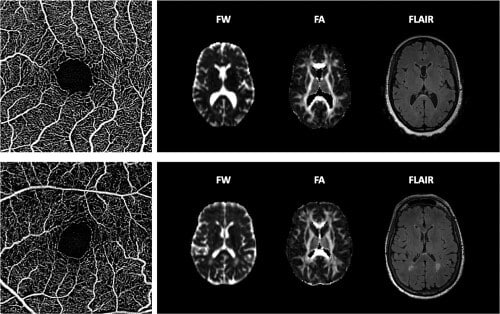

Microvascularizarea retiniană și cerebrală au caracteristici embriologice, anatomice, fiziologice și patologice similare. Această asemănare creează o oportunitate de a studia microvascularizarea cerebrală prin imagistica retiniană. Patologiile microvasculare retiniene detectabile prin fotografia retiniană au fost asociate cu tulburări cognitive și boli cerebrovasculare, cum ar fi accidentul vascular cerebral.

Angiografia asociată cu tomografia în coerență optică (OCTA) este un modalitate de imagistică aprobată recent de FDA. Spre deosebire de angiografia cu fluoresceină, care necesită injectarea intravenoasă de colorant, OCTA permite imagistica neinvazivă de înaltă rezoluție in vivo a capilarelor retiniene, cuantificarea obiectivă a modificărilor perfuziei retiniene și detectarea precoce a modificărilor vasculare înainte de manifestările clinice și, prin urmare, are potențialul  unui instrument util de screening pentru tulburările cognitive vasculare.

Perfuzia retiniană mai scăzută a fost asociată cu anomalii ale perfuziei cerebrale și tulburări cognitive în rândul subiecților, cu risc crescut de boală a vaselor mici cerebrale. Pe baza acestor constatări, este posibil ca angiografia asociată cu tomografia în coerență optică să surprindă în linii mari manifestările microvasculare ale diferitelor riscuri vasculare. factori (de exemplu, diabet, hipertensiune arterială ) și, prin urmare, servesc ca biomarker al tulburărilor cognitive vasculare.